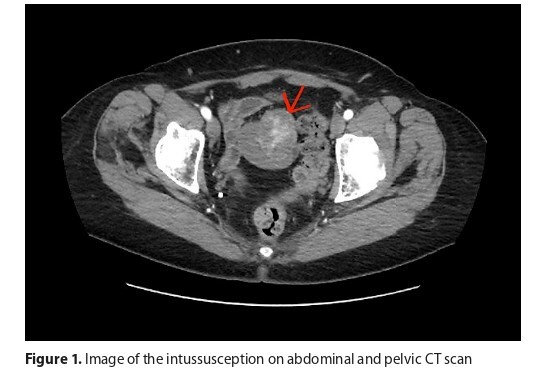

The report concerns an unusual case of a patient referred to hospital with abdominal pain and suspected

ileocecal intussusception. Ileus was confirmed during diagnostic evaluation. Surgical resection of the tumour mass was performed to release intestinal loops. Based on histology and immunohistochemical staining, GIST was diagnosed. Currently, the patient remains under constant clinical monitoring.